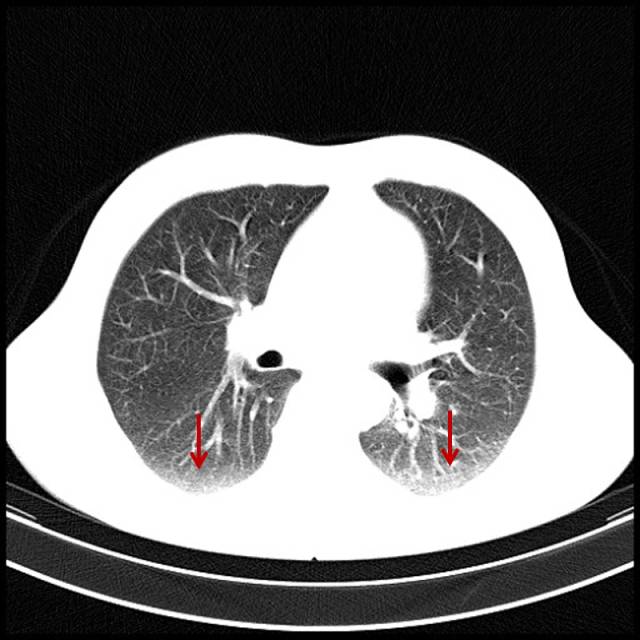

2.吸烟导致的肺坠积效应

男,35岁,吸烟,最明显感觉是游泳憋气困难。

图片

图14

肺气肿伴双肺坠积效应。此类患者用平片判断肺有无改变是要漏诊的。所以对于一个吸烟者,如果怀疑肺部有病变,平片正常仍需做CT进一步检查。